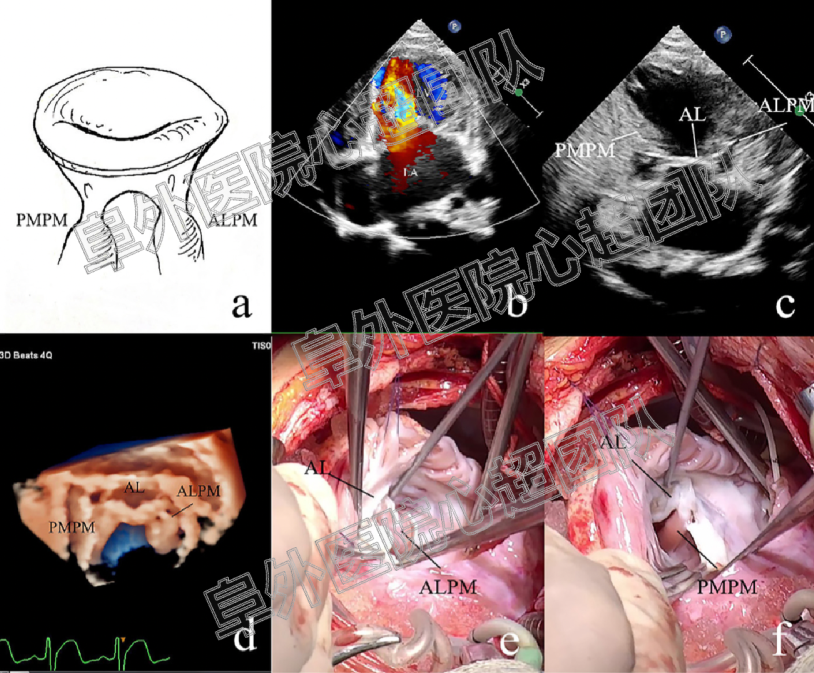

1. 共纳入207例患者,86例患儿超声诊断为UCMV(41.6%),其中77例接受了二尖瓣成形手术:75例通过手术明确诊断为UCMV(40.5%),1例患儿诊断为二尖瓣脱垂,1例患儿为功能性MR。121例患儿超声诊断其他类型的二尖瓣病变,其中110例进行了二尖瓣成形或置换手术。对于UCMV病变的诊断超声和手术结果呈现较高的一致性(kappa = 0.857, p < 0.001)。下图分别显示三种类型的UCMV的二维和三维超声心动图以及术中探查的结果。

Class I

Class II

UCMV疾病谱涵盖了二尖瓣拱廊及其一系列相关的非典型病变(如半二尖瓣拱廊、部分吊床样二尖瓣),其胚胎学机制被认为是二尖瓣在胶原化腱索衰减和延长之前发育停滞的结果。根据病变腱索的情况及是否合并MS,将UCMV分为三型,从I型到III型病变的程度是逐渐加重的,这表明二尖瓣腱索发育停止发生的时间越来越早,因此,III型患者的二尖瓣功能障碍更重,手术预后更差。典型二尖瓣拱廊的解剖与UCMV III型以及一部分II型是相似的。拱廊由两组肥厚的乳头肌和纤维桥组成,纤维桥由二尖瓣前叶增厚的下缘和中间的腱索组成。纤维桥在某些患者中并不典型,因此不作为UCMV的诊断标准。典型的先天性MS归属于III型UCMV。UCMV的另一个显著特点是所有的类型中ALCT都与腱索分布不良相关,而不存在PMCT单独病变的情况,可能是由于PMCT的腱索发育较ALCT完成的更早。UCMV I型的解剖特点和既往文献中所描述的降落伞样二尖瓣的病变是非常相似的。因此,我们认为,UCMV构成了儿童二尖瓣发育不良的主要发病机制。肥大延长的乳头肌和明显缩短或缺失的腱索,导致瓣叶的移位,瓣叶运动受限、对合缘较少从而引起二尖瓣返流或狭窄。